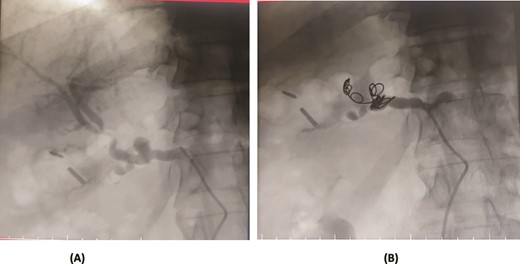

A 57-year-old female underwent a distal pancreatectomy for a pancreatic neuroendocrine tumo. On the 13th postoperative day, the patient presented in a state of shock and intraperitoneal bleeding. A contrast-enhanced CT angiogram revealed the presence of a pseudoaneurysm originating from the splenic artery. The patient underwent endovascular coil embolization of the splenic artery and bleeding stopped and was discharged 3 days following the procedure (Fig. 1).

Case 1. (A) Angiogram pseudoaneurysm from splenic artery. (B) Angioembolization of splenic artery with coil